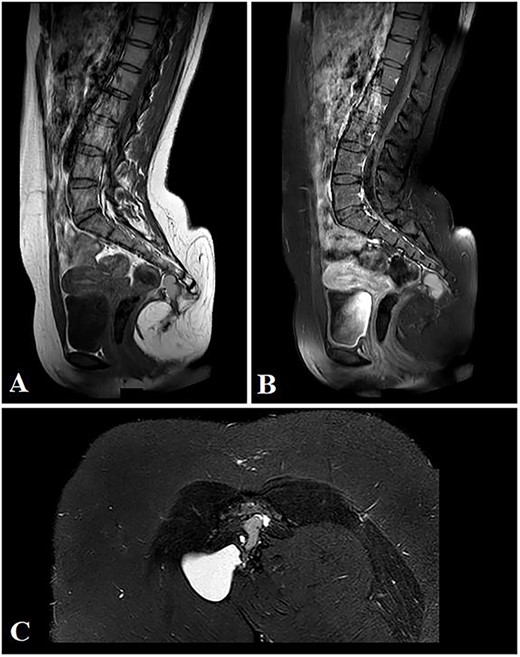

Magnetic resonance imaging (MRI) showed that the mass is mainly extra-pelvic and composed of mixed cystic and solid components. Minimal pre-coccygeal extension is noted suggesting type 1 SCT (Fig. 3).

Selected sagittal MRI images (T1-sequence) without (A) and with contrast (B), both showing the extension of the mass with a visible pre-coccygeal component. The tumor is seen composed of mixed solid (predominantly fat) and cystic (fluid) components. The cystic component appears hyper-intense on the STIR sequence (C).